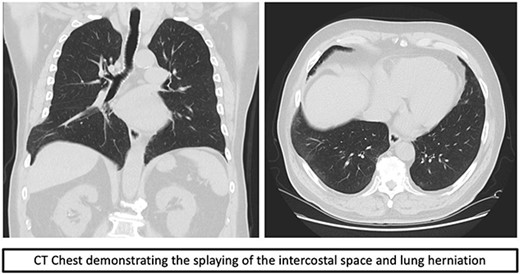

Over time, the bruising subsided, however he continued to have a bulge and localized pain. A CT scan of the chest revealed splaying of the eighth and ninth ribs with bulging of lung and perihepatic fat consistent with herniation (Fig. 1). He was referred to Thoracic surgery outpatient clinic for consideration of surgical management due to ongoing symptoms.